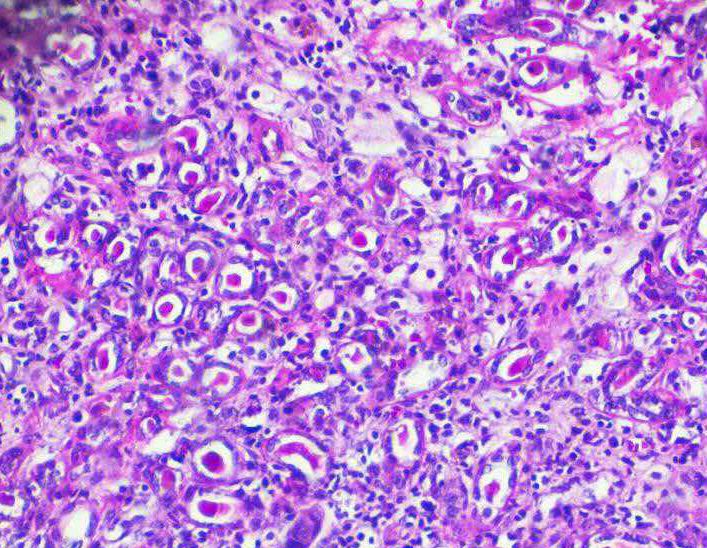

近年来,2个代谢酶--异柠檬酸脱氢酶1和异柠檬酸脱氢酶2(IDH1和IDH2)的突变,已被确定在大约20%的急性粒细胞性白血病(AML)中存在...